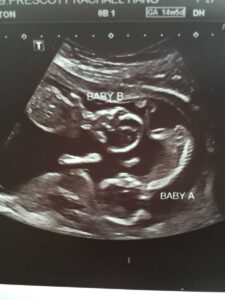

At our first appointment with a midwife, I waved goodbye to familiarity. Stunned, I propped up in disbelief, listening to the crowded sound of the Doppler’s drumming. Two babies? My husband was (ironically) ecstatic. Twins!? This would require some serious adjustments. We would need another car seat. Two bedrooms would no longer be realistic, for a family of six. Prenatally, ‘multiples’ equate to an increase of risk and therefore more ultrasounds. We had no idea what the first one had instore.

‘Look at our sweet girls!’ we cooed. Two identical, squirmy bodies were being studied on the screen of a fetal echocardiogram. Meanwhile, our boys chowed down on goldfish off to the side, watching now their second movie. This was taking a long time. Had the last ultrasound been this quiet? My eyes scrutinized the facial expressions of each technician, as they captured images of the gray/black screen, once more dancing with reds and blues. This day we discovered both of our daughters had Congenital Heart Disease, and were forecasted to require open heart surgery possibly at birth. Additionally, with this discovery arose a possibility of the girls having Down syndrome.